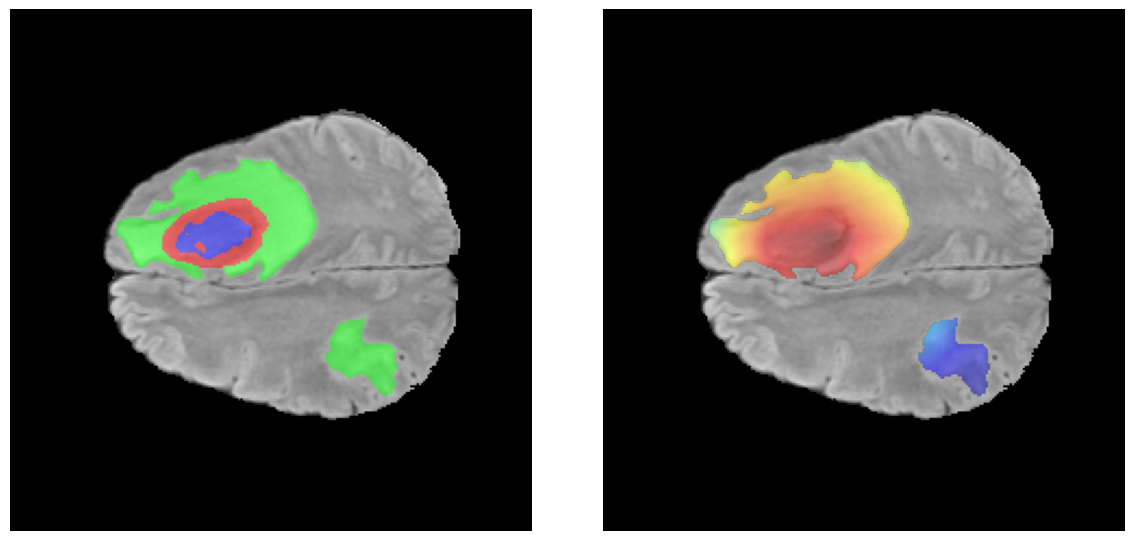

Mapas de Explicabilidad (Grad-CAM++)

Visualización de las regiones de atención del modelo que validan su razonamiento clínicamente relevante

Ejemplos HGG - Atención en Núcleo Necrótico y Tumor Realzado

HGG Grad-CAM++ 1 HGG Grad-CAM++ 2 HGG Grad-CAM++ 3 HGG Grad-CAM++ 4 HGG Grad-CAM++ 5 HGG Grad-CAM++ 6

Los heatmaps muestran que el modelo concentra su atención en las regiones de Tumor Realzado (rojo) y Núcleo Necrótico (azul), características patológicas clave de los gliomas de alto grado.

Ejemplos LGG - Atención Difusa en Edema Peritumoral

LGG Grad-CAM++ 1 LGG Grad-CAM++ 2 LGG Grad-CAM++ 3 LGG Grad-CAM++ 4 LGG Grad-CAM++ 5 LGG Grad-CAM++ 6

Para casos LGG, la atención del modelo es más difusa y se concentra principalmente en la región de Edema Peritumoral (verde), consistente con la naturaleza más infiltrativa y menos agresiva de estos tumores.

Validación con IA Explicable

El análisis Grad-CAM++ reveló que el modelo desarrolla automáticamente la capacidad de localizar las regiones tumorales. Para casos HGG, la atención se alinea fuertemente con las regiones de Tumor Realzado (ET) y Núcleo Necrótico (NCR). En contraste, los casos LGG muestran atención más difusa, principalmente concentrada en la región de Edema Peritumoral (ED), lo cual es consistente con la patofisiología conocida de los gliomas.

✅ Validación con IA Explicable